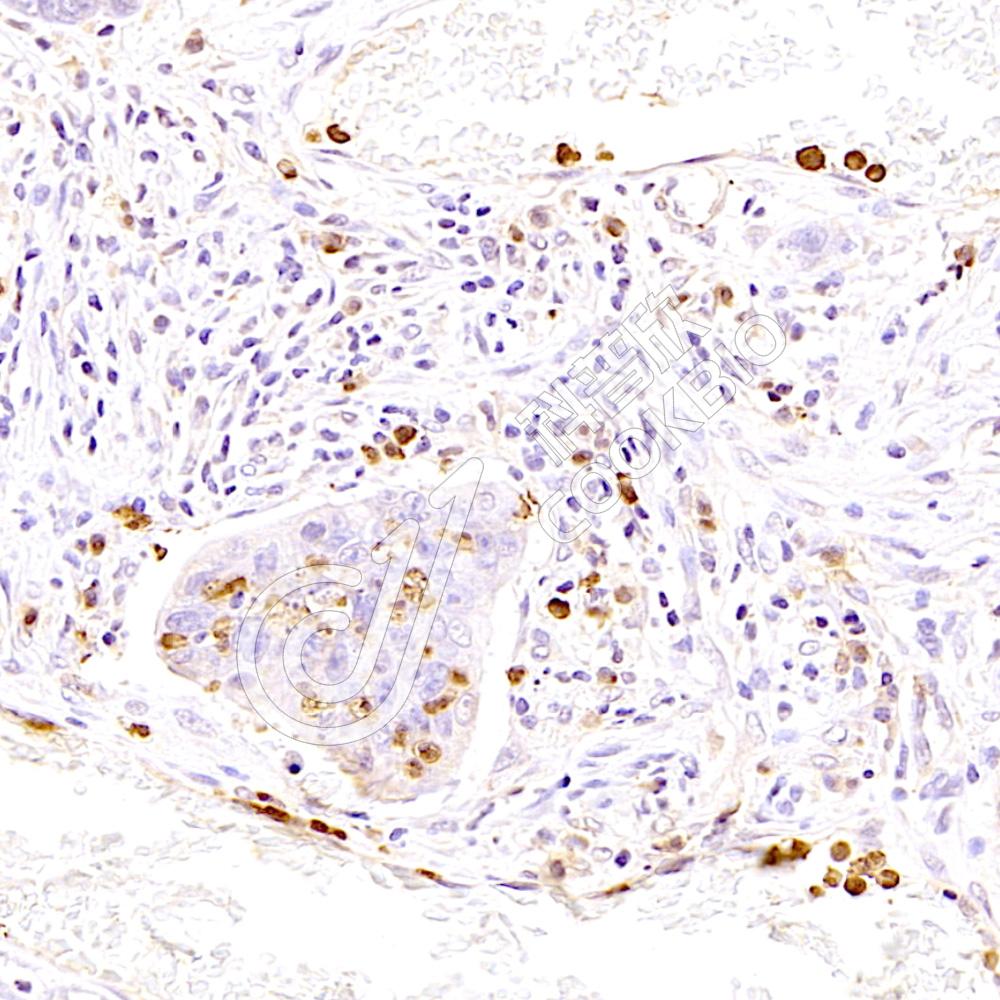

IHC检测Proteasome 20S beta 6蛋白(货号 K1335853).

样品: 人结肠癌, 4%多聚甲醛 (货号KSG1101) 固定12-24小时.

抗原修复: 柠檬酸抗原修复液(干粉, pH 6.0) (KSG1201), 98℃, 20分钟.

—抗: 1: 900稀释, 4℃ 孵育过夜.

二抗: S-vision免疫组化多聚二抗(山羊抗兔),即用型 (货号KB3906), 室温孵育20分钟.